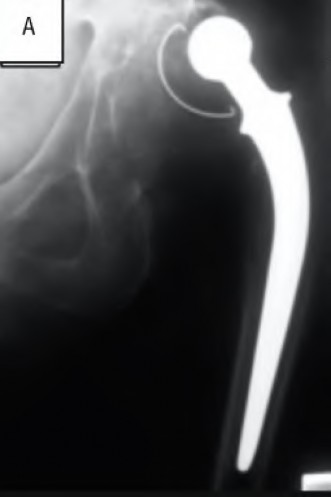

A 45-year-old female with developmental dysplasia of the hip (DDH) presents for THA. Preoperative radiographs show the femoral head is subluxated, with 80% proximal migration relative to the height of the normal true acetabulum. Based on the Crowe classification, what type of dysplasia does she have?